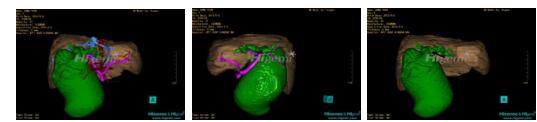

10、三维重建虚拟肝脏、胆道显像技术

三维虚拟肝脏技术是在二维影像学资料如CT等图像的基础上,通过三维重组软件和工具,比如青岛大学附属医院与海信医疗集团联合自主研发的海信计算机辅助手术系统(Hisense Computer Assisted Surgery,Hisense CAS),目前已投入临床并指导实际应用,利用该类系统对二维影像学的数据资料进行三维立体分析,重组形成立体的、有空间结构的、虚拟的肝脏三维图像。这项技术较传统的二维平面成像技术,有着明显的优势,3D虚拟肝脏技术可以构造出一个虚拟的、可视化的肝脏模型。通过对这种模型的观察,可以很容易地分辨出肝脏器官的组织结构、解剖特点,直观研究肝外胆总管的形态差异,明确肝内胆管的形态、走形、是否合并扩张、狭窄及结石,胰胆管合流的形态及共同通道内是否有狭窄、扩张和结石等病变情况,预先规划处理可能合并存在的肝内胆管扩张、狭窄或其他复杂胆道畸形,清晰地显示肝内脉管系统,包括门静脉、肝动脉及肝静脉的走行、分支,并可多角度、全方位观察病变胆道与其周围重要血管尤其是伴行的门静脉之间的解剖关系,大大提高了外科医师在术前对肝脏内部各管道结构及其变异判断的精确性和可靠性,精准地对病变进行判断和评估,还可根据患者自身的病变特点,制定出合理、个体化的手术方案,最大限度地降低术中和术后并发症发生率,并术中导航实时指导手术,提高手术的精准性和成功率。

图11:先天性胆管扩张症梭状型三维重建虚拟肝脏、胆道显像

a 图为术前二维CT扫描图像,箭头指示肝内胆管扩张;b 图为CT经多平面重组技术(MPR)所得的重建图像,可粗略地判断病变胆管的位置;c 图示术前Hisense CAS三维重建清晰显示胆管的病理形态及其与肝内三套血管系统的解剖关系;d 图示胆道系统与其伴行的门静脉系统的空间解剖关系;e 图为胆道系统立体形态,箭头处指示迷走胆管,源自肝脏直接汇入胆总管。术前规划先将迷走胆管与肝总管吻合成形,再行肝总管空肠Roux-en-Y吻合术。

图12:先天性胆管扩张症梭状型合并左右肝管分别汇入胆总管囊肿三维重建虚拟肝脏、胆道显像

a 图为术前二维CT图像;b 图为CT经多平面重组技术(MPR)所得的三维重建图像,可粗略地判断病变胆管的位置;c 图为MRCP显示胆总管梭状扩张;d 图为术前Hisense CAS三维重建显示胆管的分布走形及其与肝内三套血管系统的解剖关系;e 图为胆道系统立体形态及与肝脏整体的空间关系,箭头处显示对于左右肝管分别汇入胆总管囊肿中,整个肝总管也明显扩张而成为囊肿的一部分。术前规划为先将囊肿完全切除,左右肝管合并成形后再与空肠吻合。